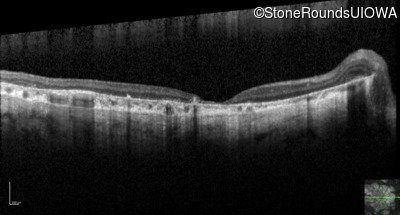

Optical Coherence Tomography - Right - 10/125 sc

Exemplar / OCT Stack